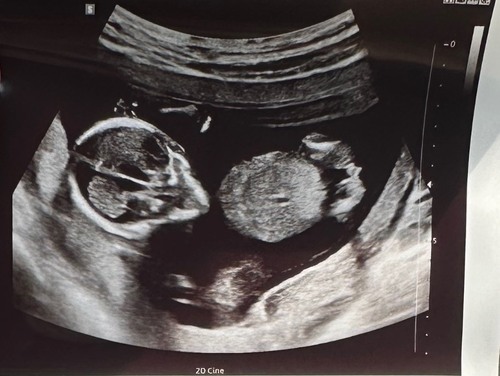

Ik denk ook een jongetje. Wij krijgen een meisje en dat zag er anders uit op de 13 weken echo.